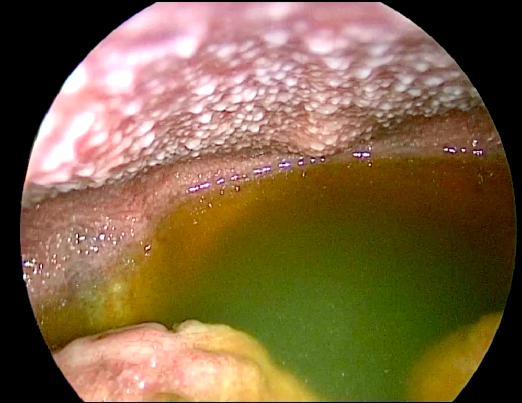

What pathology is shown in what region of the body?

Laproscopic image, showing portion of the bowel at the bottom of the image and peritoneal fluid, far more than normally should be there.

On the posterior abdominal wall there are deposits of TB infection.